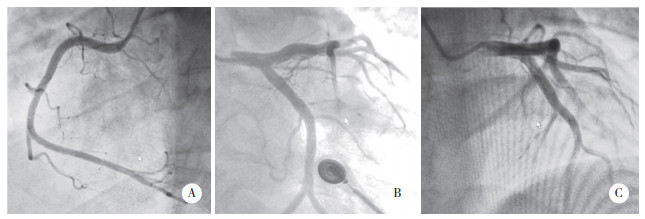

患者于我院急诊完善心电图(2019年5月8日16:33),提示Ⅱ、Ⅲ、aVF、V5-6导联可见ST段抬高0.1~0.2 mV(图 1)。体格检查未见异常阳性体征,体温36.5 ℃,脉率82次/min,呼吸20次/min,血压123/79 mmHg。急诊行冠状动脉造影(2019年5月8日17:15),提示前降支7号段轻度肌桥,余血管未见异常(图 2),急诊行左心室造影,未见异常。

| A,右冠状动脉未见异常;B,左主干、回旋支、前降支未见异常(收缩期可见轻度肌桥);C,前降支、回旋支未见异常. 图 2 急诊冠状动脉造影结果 |